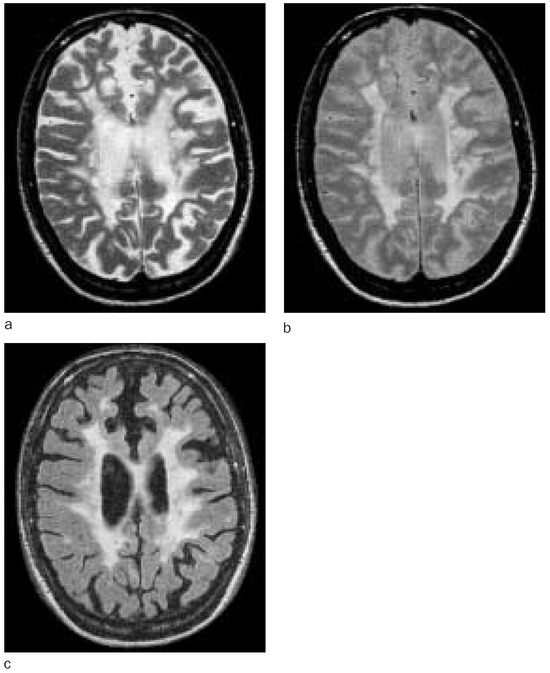

Stellenwert der Magnetresonanztomographie bei Diagnose und Krankheitsmonitoring der Multiplen Sklerose

by P. Freitag, L. Kappos and E. W. Radü

Magnetic resonance imaging (MRI) is currently the best method for imaging multiple sclerosis. Although there is only a weak correlation between clinical disease evolution and conventional magnetic resonance imaging findings, it is a very sensitive method which provides important additional information both in individual case studies and in therapeutic trials. In this review the impact of MRI in diagnosis, prognosis, follow-up and treatment control in multiple sclerosis patients is shown with respect to the different disease courses. More re-cent MR techniques like magnetisation transfer imaging, proton magnetic resonance spectroscopy, measurements of atrophy, functional magnetic resonance imaging (fMRI) and diffusion weighted magnetic resonance imaging are explained. Their contribution for the understanding of pathophysiological and pathoanatomical disease processes in multiple sclerosis and the improvement of clinical correlation between MRI and disease course is discussed. Full article

Show Figures

Figure 1